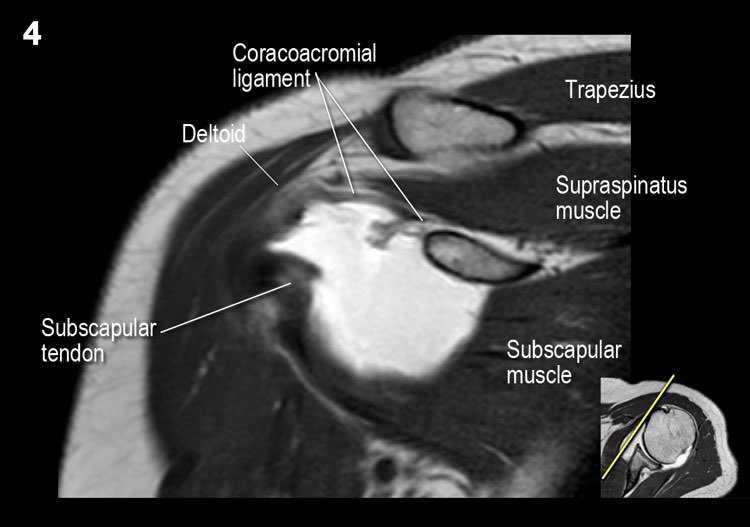

Giải phẫu mặt cắt vành và danh sách kiểm tra

- Lưu ý dây chằng quạ-đòn và đầu ngắn cơ nhị đầu.

- Lưu ý dây chằng quạ-mỏm cùng vai.

- Lưu ý thần kinh và mạch máu trên vai.

- Tìm kiếm hội chứng chèn ép cơ trên gai do gai xương khớp cùng-đòn hoặc dây chằng quạ-mỏm cùng vai dày lên.

- Đánh giá phức hợp sụn viền-gân cơ nhị đầu phần trên và tìm kiếm túi cùng dưới sụn viền hoặc rách SLAP.

- Tìm kiếm tràn dịch quá mức trong túi hoạt dịch dưới mỏm cùng vai và rách gân cơ trên gai.